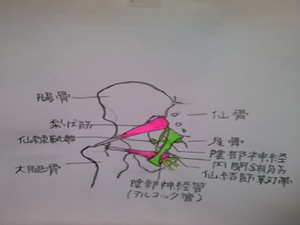

座っていることにより、骨盤底筋群の圧迫、陰部神経の絞扼、尾骨を奥に潰されて固着しており、それが前立腺に影響を与えています。それに伴い骨盤底筋(尾骨から恥骨に付いている筋肉)の機能障害、殿筋から股関節周りの筋肉、ハムストリングに影響を与えています。

前立腺は膀胱の下で尿道を取り囲むように存在し、骨盤の一番奥にある器官です。体表からは陰嚢と肛門の間の皮膚の数cm奥のあたりに存在します。

座っていることにより、骨盤底筋群の圧迫、陰部神経の絞扼、尾骨を奥に潰されて固着しており、それが前立腺に影響を与えています。それに伴い骨盤底筋(尾骨から恥骨に付いている筋肉)の機能障害、殿筋から股関節周りの筋肉、ハムストリングに影響を与えています。

尾骨整復、骨盤底筋調整、骨盤調整になります。